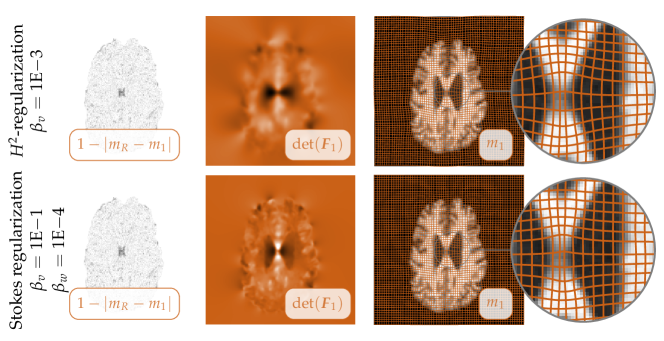

Fig. 3: Exemplary registration results for the multisubject brain images (see Fig. 1). We report representative results from Tab. 2. We report results for plain smoothness regularization (top row; H2superscript𝐻2H^{2}-regularization; γ=0𝛾0\gamma=0; βv=1E2subscript𝛽𝑣1E-2\beta_{v}=$110-2$) and for a model with local adaptive compression (bottom row; H1superscript𝐻1H^{1}-regularization; γ=1𝛾1\gamma=1; βv=1E1subscript𝛽𝑣1E-1\beta_{v}=$110-1$; βw=1E4subscript𝛽𝑤1E-4\beta_{w}=$110-4$). We display (from left to right) (i𝑖i) a map of the residual differences after registration, (ii𝑖𝑖ii) a map of the determinant of the deformation gradient (the values are reported in Tab. 2; information about the color map can be found in §D of the appendix), (iii𝑖𝑖𝑖iii) the deformed template image m1subscript𝑚1m_{1} with a grid in overlay (to illustrate the deformation map 𝒚𝒚\boldsymbol{y}), and (iv𝑖𝑣iv) a close up of the latter for a particular area of interest (as identified by the inset in the images).